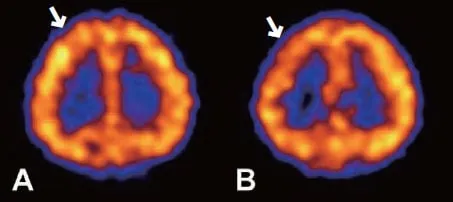

두개 내 양측 내경동맥 말단부위나 주요 가지 동맥의 점차적인 폐쇄로 특징적인 소견을 통해 진단합니다. 뇌 혈관 조영술에서 연기 같은 미세한 혈관들이 관찰되면 모야모야병으로 진단됩니다. 뇌혈역학적 검사(SPECT)를 통해 혈역학적 스트레스 정도를 평가하고 치료 방침을 결정합니다.